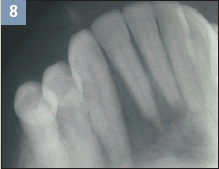

Figure 8. Radiograph showing metastatic squamous

cell carcinoma to the anterior mandible. |

During the soft tissue examination, the dental hygienist can describe and measure the lesion, identify the exact location, and review the patient’s dental history to determine if any previous notations were made. In Figures 6 and 7, an exophytic mass (showing growth from the surface) is shown that is ulcerated with indurated borders (hardness due to the growth of epithelial cells resulting from inflammation). After biopsy and microscopic examination, a diagnosis is made of these more advanced lesions of squamous cell carcinoma. Squamous cell carcinoma can metastasize to the lymph nodes, lungs, liver, or bone. In the jaws, the mandible (Figure 8) is most likely the site of metastasis. A radiograph alone cannot determine a diagnosis for squamous cell carcinoma.